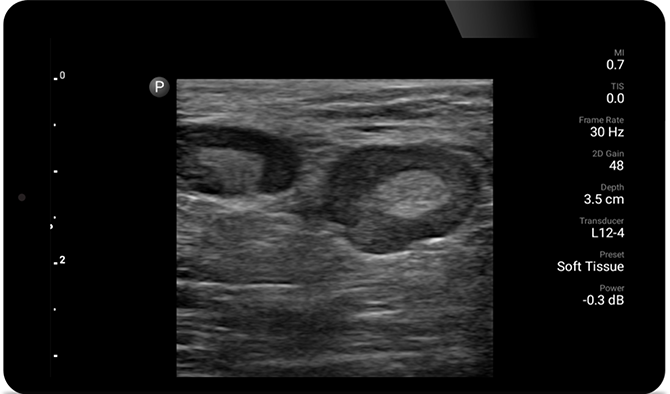

Hautabszesse lassen sich mit Ultraschall mitunter leichter erkennen und erfolgreich behandeln.

POC ultrasound for soft tissue (Weichgewebe-Ultraschall am Point of Care)